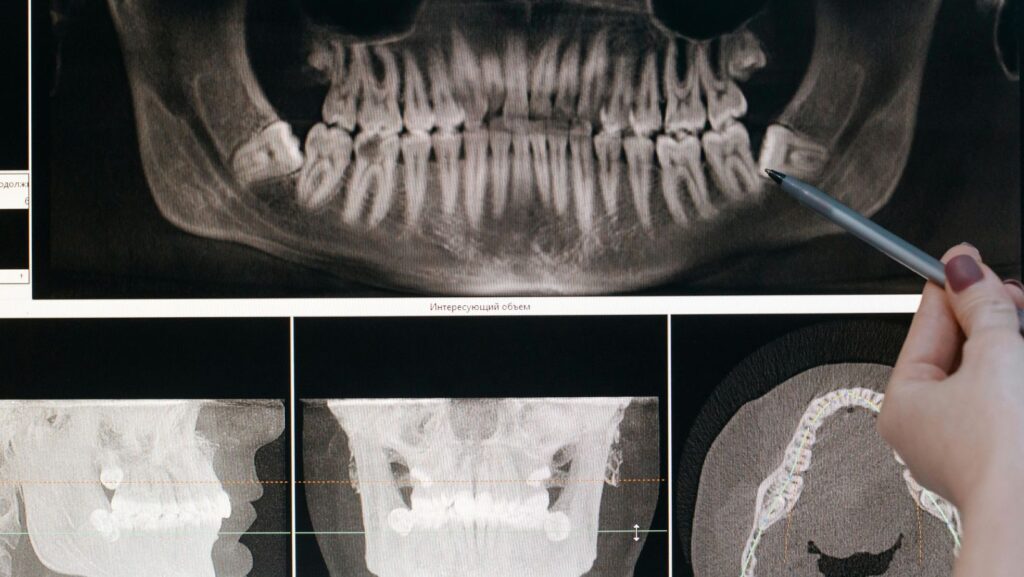

During your consultation at CU Dentists in Champaign IL, your dentist will examine your mouth, take X-rays or scans, and discuss all available treatment options. The goal is to find a solution that balances comfort, aesthetics, and long-term health.